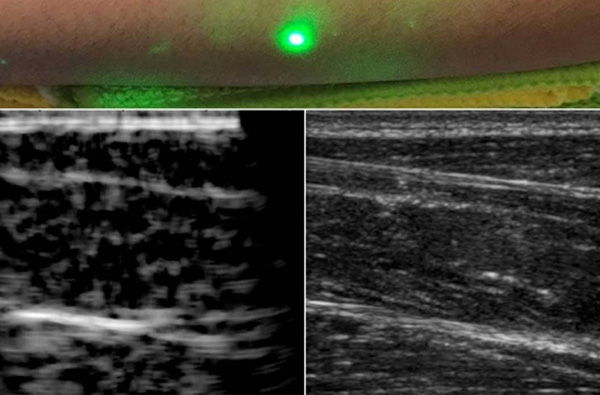

全球首張人類激光超聲波圖像問世

東莞盈創(chuàng)激光科技有限公司,詳細(xì)概述,與其他成像方法相比,超聲成像具有非電離、成本相對較低、便于攜帶等優(yōu)點(diǎn)。 如果需要進(jìn)行超聲波檢查,但患者不能忍受探針接觸皮膚,例如嬰兒或燒傷患者,則需要更好的技術(shù)。 現(xiàn)在,麻省...